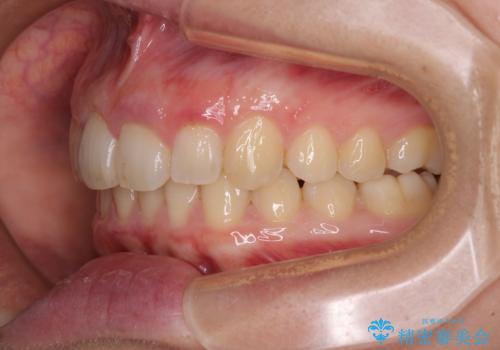

- 八重歯を気にして来院された患者様です。

八重歯の後ろの歯を1歯抜歯し、補助装置(リンガルアーチ)を用いて八重歯の位置を改善し、その後インビザラインにより矯正治療を行うこととしました。

下顎前歯が1本欠損したスリーインサイザーという状態であるため、上下の前歯の咬み込みが深くなったり、奥歯の咬み合わせが理想的なものとならなかったりという仕上がりになってしまいます。

前歯の見た目や奥歯の咬み合わせに、患者様が違和感を感じない状態として治療を終えました。